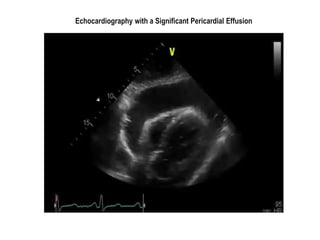

Echocardiography with a Significant Pericardial Effusion

Echocardiography with aSignificant Pericardial Effusion